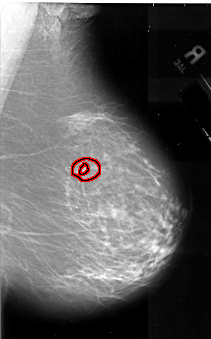

FILE: A_1070_1.RIGHT_CC.OVERLAY

TOTAL_ABNORMALITIES 1

ABNORMALITY 1

LESION_TYPE MASS SHAPE IRREGULAR MARGINS SPICULATED

ASSESSMENT 5

SUBTLETY 2

PATHOLOGY MALIGNANT

TOTAL_OUTLINES 2

BOUNDARY

CORE